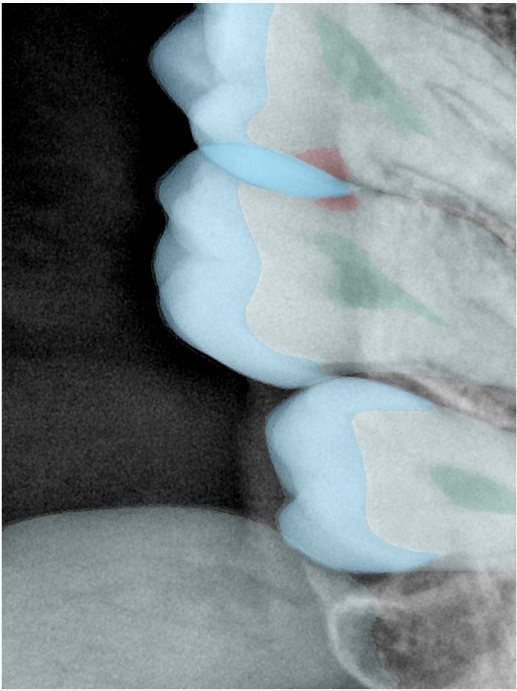

第三版算法分辨率效果比较

Updated: 2026-04-13(更新日期)

| 编号 | 原图 | 第一版 | 第二版 | 第三版 1216x1600 | 第三版 768x1024 | 第三版 1120x1120 |

|---|---|---|---|---|---|---|

| 131315.jpg | ![]() | ![]() | ![]() | ![]() | ![]() | ![]() |

| 131316.jpg | ![]() | ![]() | ![]() | ![]() | ![]() | ![]() |

| 131317.jpg | ![]() | ![]() | ![]() | ![]() | ![]() | ![]() |

| 131318.jpg | ![]() | ![]() | ![]() | ![]() | ![]() | ![]() |

| 131319.jpg | ![]() | ![]() | ![]() | ![]() | ![]() | ![]() |

| 131320.jpg | ![]() | ![]() | ![]() | ![]() | ![]() | ![]() |

| 131321.jpg | ![]() | ![]() | ![]() | ![]() | ![]() | ![]() |

| 131326.jpg | ![]() | ![]() | ![]() | ![]() | ![]() | ![]() |

| 131327.jpg | ![]() | ![]() | ![]() | ![]() | ![]() | ![]() |

| 131328.jpg | ![]() | ![]() | ![]() | ![]() | ![]() | ![]() |

| 131330.jpg | ![]() | ![]() | ![]() | ![]() | ![]() | ![]() |

| 131331.jpg | ![]() | ![]() | ![]() | ![]() | ![]() | ![]() |

| 131332.jpg | ![]() | ![]() | ![]() | ![]() | ![]() | ![]() |

| 131333.jpg | ![]() | ![]() | ![]() | ![]() | ![]() | ![]() |

| 131334.jpg | ![]() | ![]() | ![]() | ![]() | ![]() | ![]() |

| 131336.jpg | ![]() | ![]() | ![]() | ![]() | ![]() | ![]() |

| 131337.jpg | ![]() | ![]() | ![]() | ![]() | ![]() | ![]() |

| 131338.jpg | ![]() | ![]() | ![]() | ![]() | ![]() | ![]() |

| 131339.jpg | ![]() | ![]() | ![]() | ![]() | ![]() | ![]() |

| 131340.jpg | ![]() | ![]() | ![]() | ![]() | ![]() | ![]() |

| 131341.jpg | ![]() | ![]() | ![]() | ![]() | ![]() | ![]() |

| 131342.jpg | ![]() | ![]() | ![]() | ![]() | ![]() | ![]() |

| 131344.jpg | ![]() | ![]() | ![]() | ![]() | ![]() | ![]() |

| 131345.jpg | ![]() | ![]() | ![]() | ![]() | ![]() | ![]() |

| 131346.jpg | ![]() | ![]() | ![]() | ![]() | ![]() | ![]() |

| 131347.jpg | ![]() | ![]() | ![]() | ![]() | ![]() | ![]() |

| 131348.jpg | ![]() | ![]() | ![]() | ![]() | ![]() | ![]() |

| 131349.jpg | ![]() | ![]() | ![]() | ![]() | ![]() | ![]() |

| 131350.jpg | ![]() | ![]() | ![]() | ![]() | ![]() | ![]() |

| 131354.jpg | ![]() | ![]() | ![]() | ![]() | ![]() | ![]() |

| 131355.jpg | ![]() | ![]() | ![]() | ![]() | ![]() | ![]() |

| 131356.jpg | ![]() | ![]() | ![]() | ![]() | ![]() | ![]() |

| 131357.jpg | ![]() | ![]() | ![]() | ![]() | ![]() | ![]() |

| 131360.jpg | ![]() | ![]() | ![]() | ![]() | ![]() | ![]() |

| 131362.jpg | ![]() | ![]() | ![]() | ![]() | ![]() | ![]() |

| 131363.jpg | ![]() | ![]() | ![]() | ![]() | ![]() | ![]() |

| 131364.jpg | ![]() | ![]() | ![]() | ![]() | ![]() | ![]() |

| 131365.jpg | ![]() | ![]() | ![]() | ![]() | ![]() | ![]() |